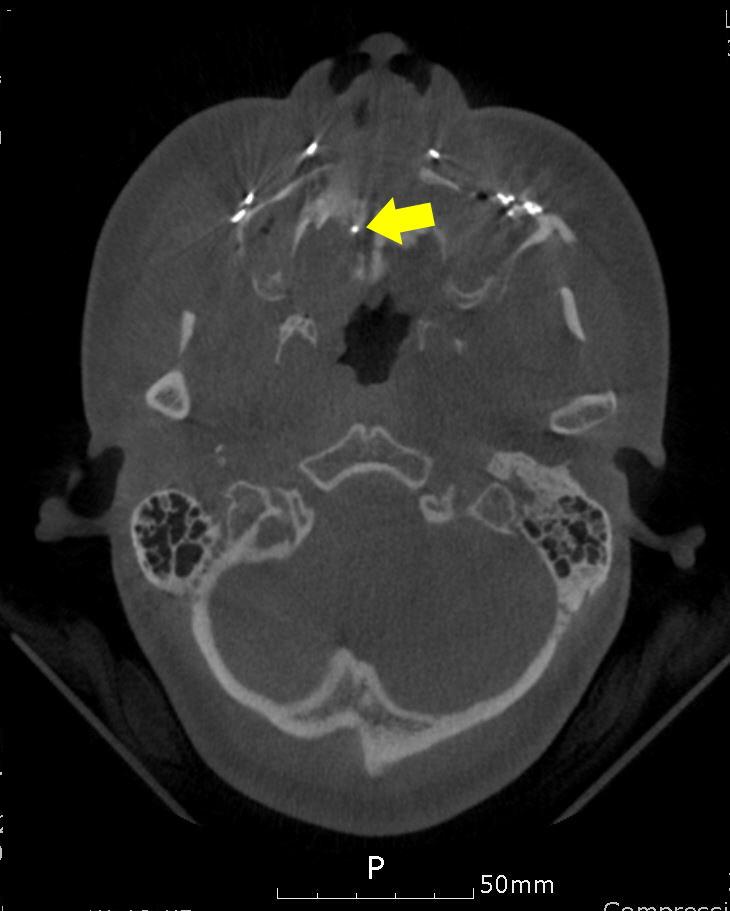

A 34-year-old female patient who underwent orthognathic surgery exhibited repeated endotracheal tube cuff tears during nasotracheal intubation. After intubation, leaks developed, and torn endotracheal cuff was observed in the removed endotracheal tube. Subsequently, re-intubation through the same nasal cavity was performed immediately, but leakage from the torn endotracheal tube cuff was re-observed. A leakage test of the extubated tube revealed air bubbles and leaks near the tube cuff due to the tear. Nasotracheal intubation was performed through the other nasal cavity, and there were no leakage findings or abnormalities. During the course of the surgery, the surgeon noticed that the orthodontic micro-implant deposited in the mid-tube cavity was exposed to the nasal cavity.

一名34岁接受正颌手术的女性患者在鼻气管插管期间出现反复的气管导管套囊撕裂。插管后出现漏气,在取出的气管导管中观察到套囊撕裂。随后,立即通过同一鼻腔重新插管,但再次观察到气管导管套囊撕裂处漏气。对拔出的导管进行漏气测试,发现由于撕裂,导管套囊附近有气泡和漏气。通过另一侧鼻腔进行鼻气管插管,未发现漏气或异常情况。在手术过程中,外科医生注意到置于中管腔内的正畸微种植体暴露于鼻腔。